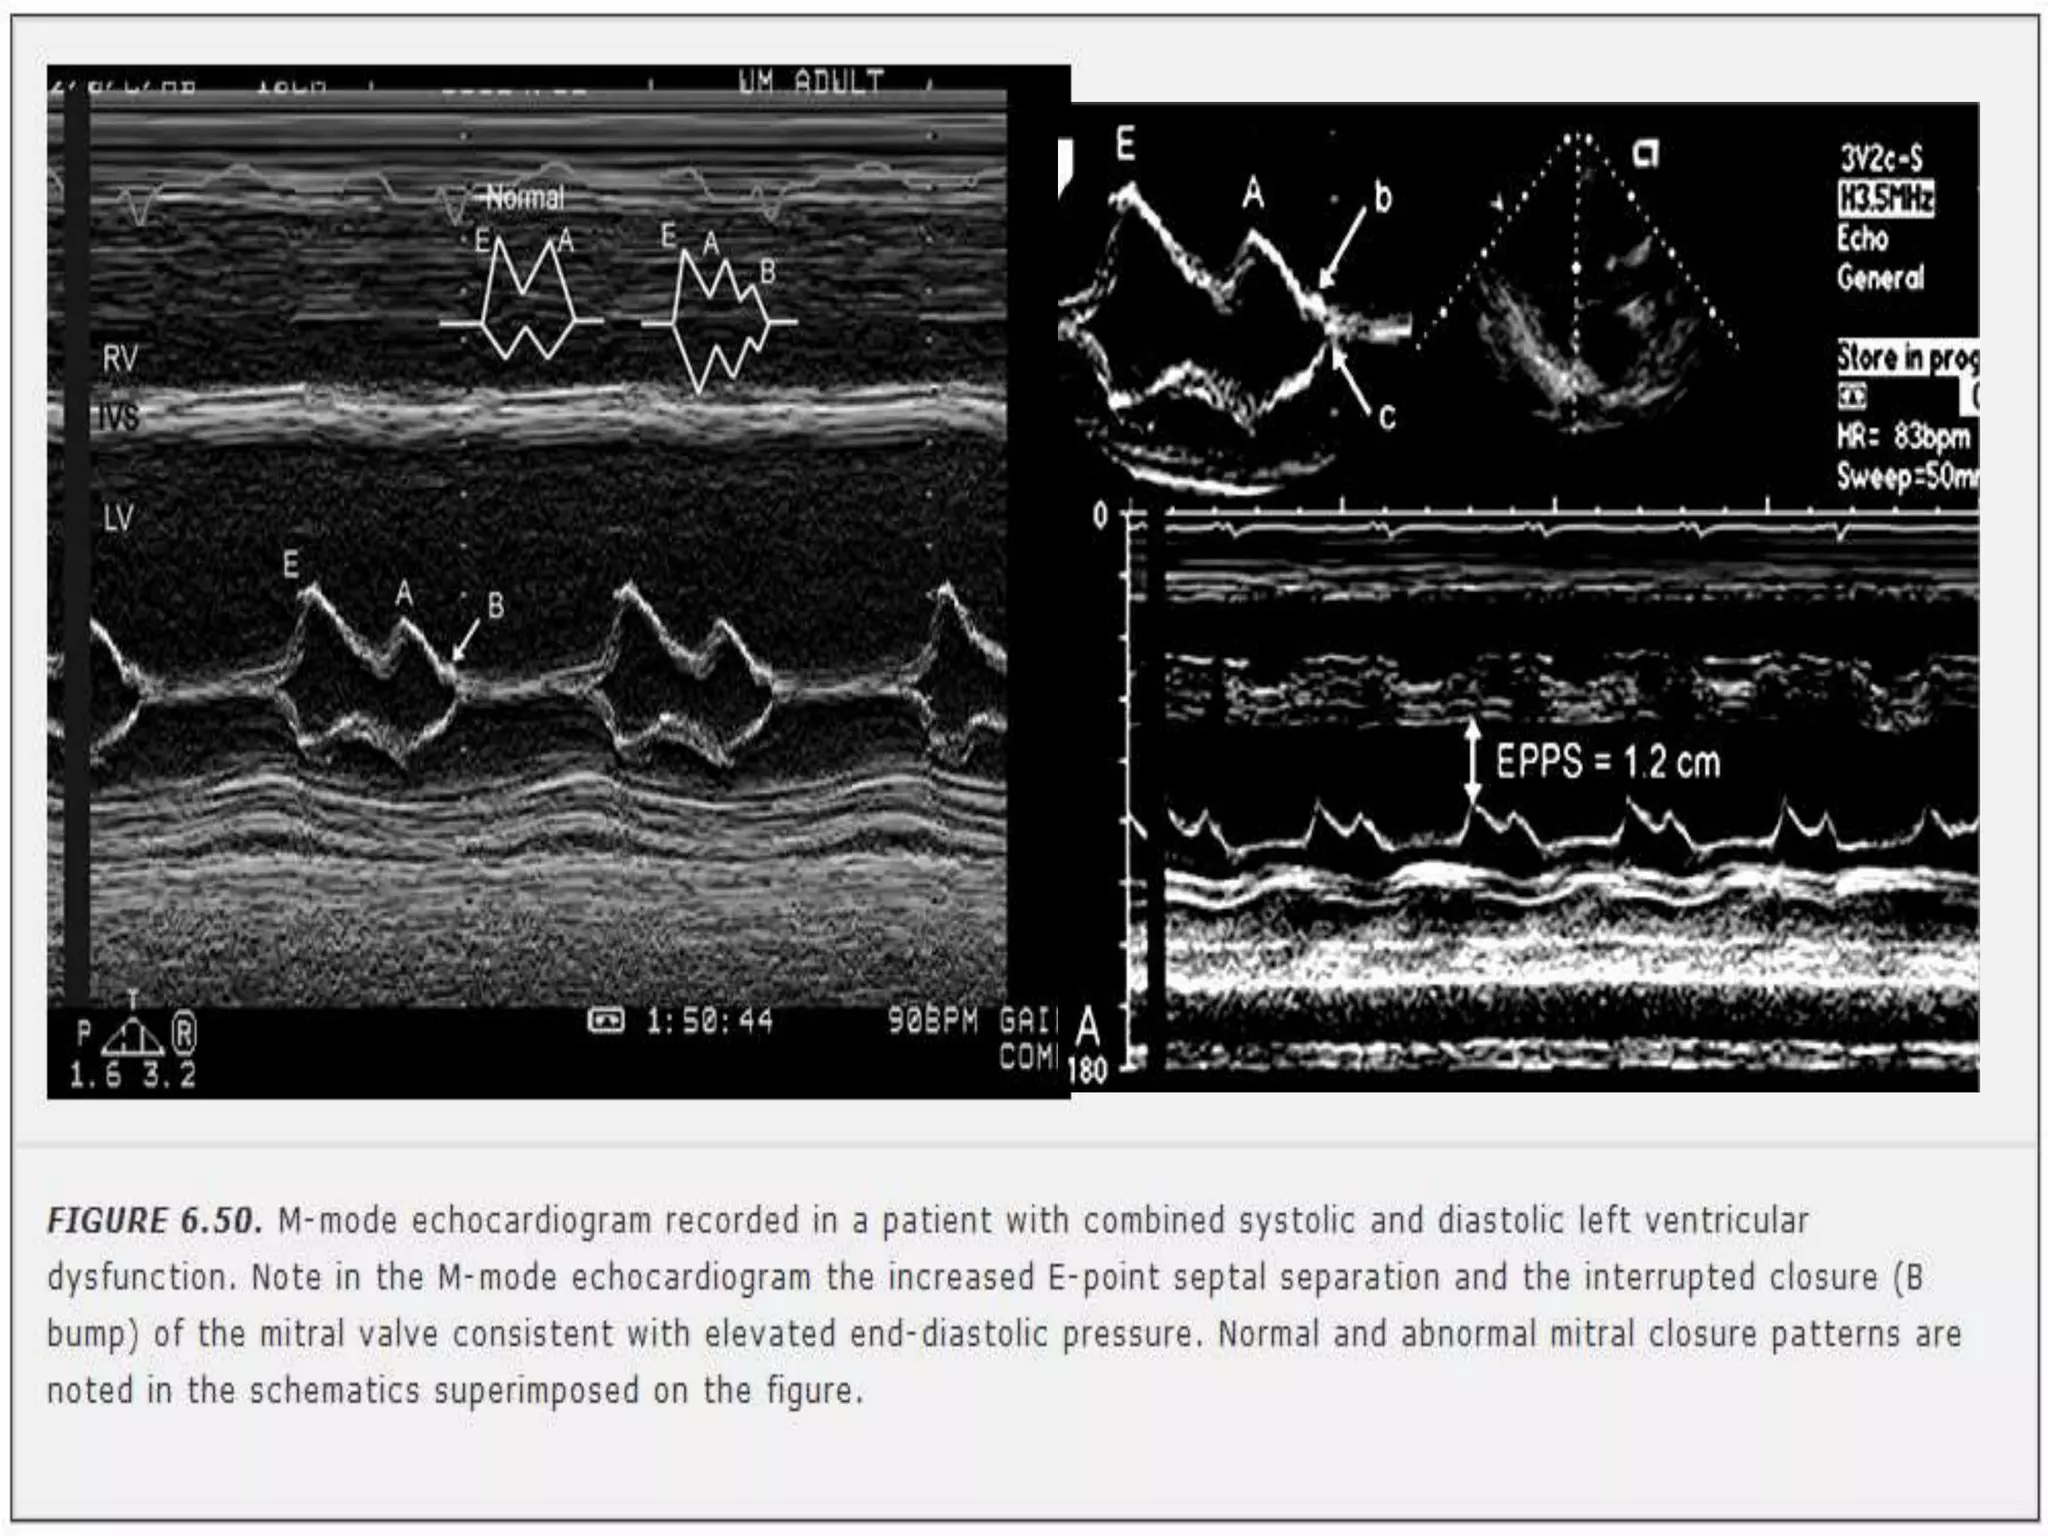

1. E-point septal separation

 magnitude of opening of the mitral valve=E-

wave height, correlates with transmitral flow

and, in the absence of significant MR, with LV

SV

 Mitral valve E point (maximal early opening) -

within 6 mm of the left side of the ventricular

septum

 decreased ejection fraction-distance is

increased

Severe systolic dysfunction